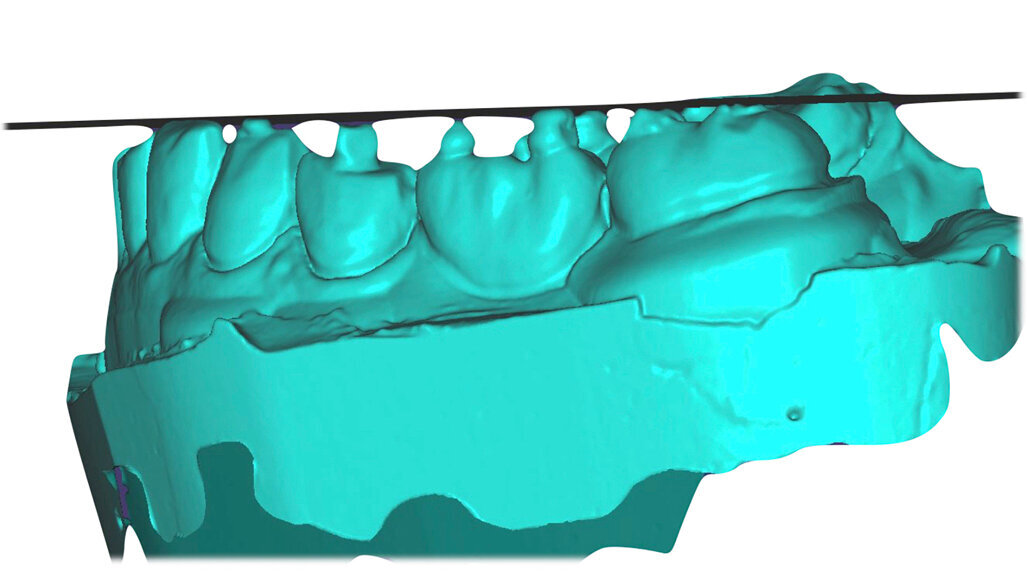

Přesné naprogramování a vosková modelace okluze se sekvenčním vedením s dominancí špičáků vyžaduje velké odborné znalosti. Účelem tohoto článku je ukázat způsob našeho využití digitálních postupů při diagnostice vycházejících z CAD programování okluze a výroby protetických konstrukcí pomocí CAM – to vše s cílem zjednodušit mana­gement složitých výrobních procesů. Tyto postupy vedou k větší individualizaci designu okluze u nově vznikající skupiny pacientů s narušenou funkcí chrupu.